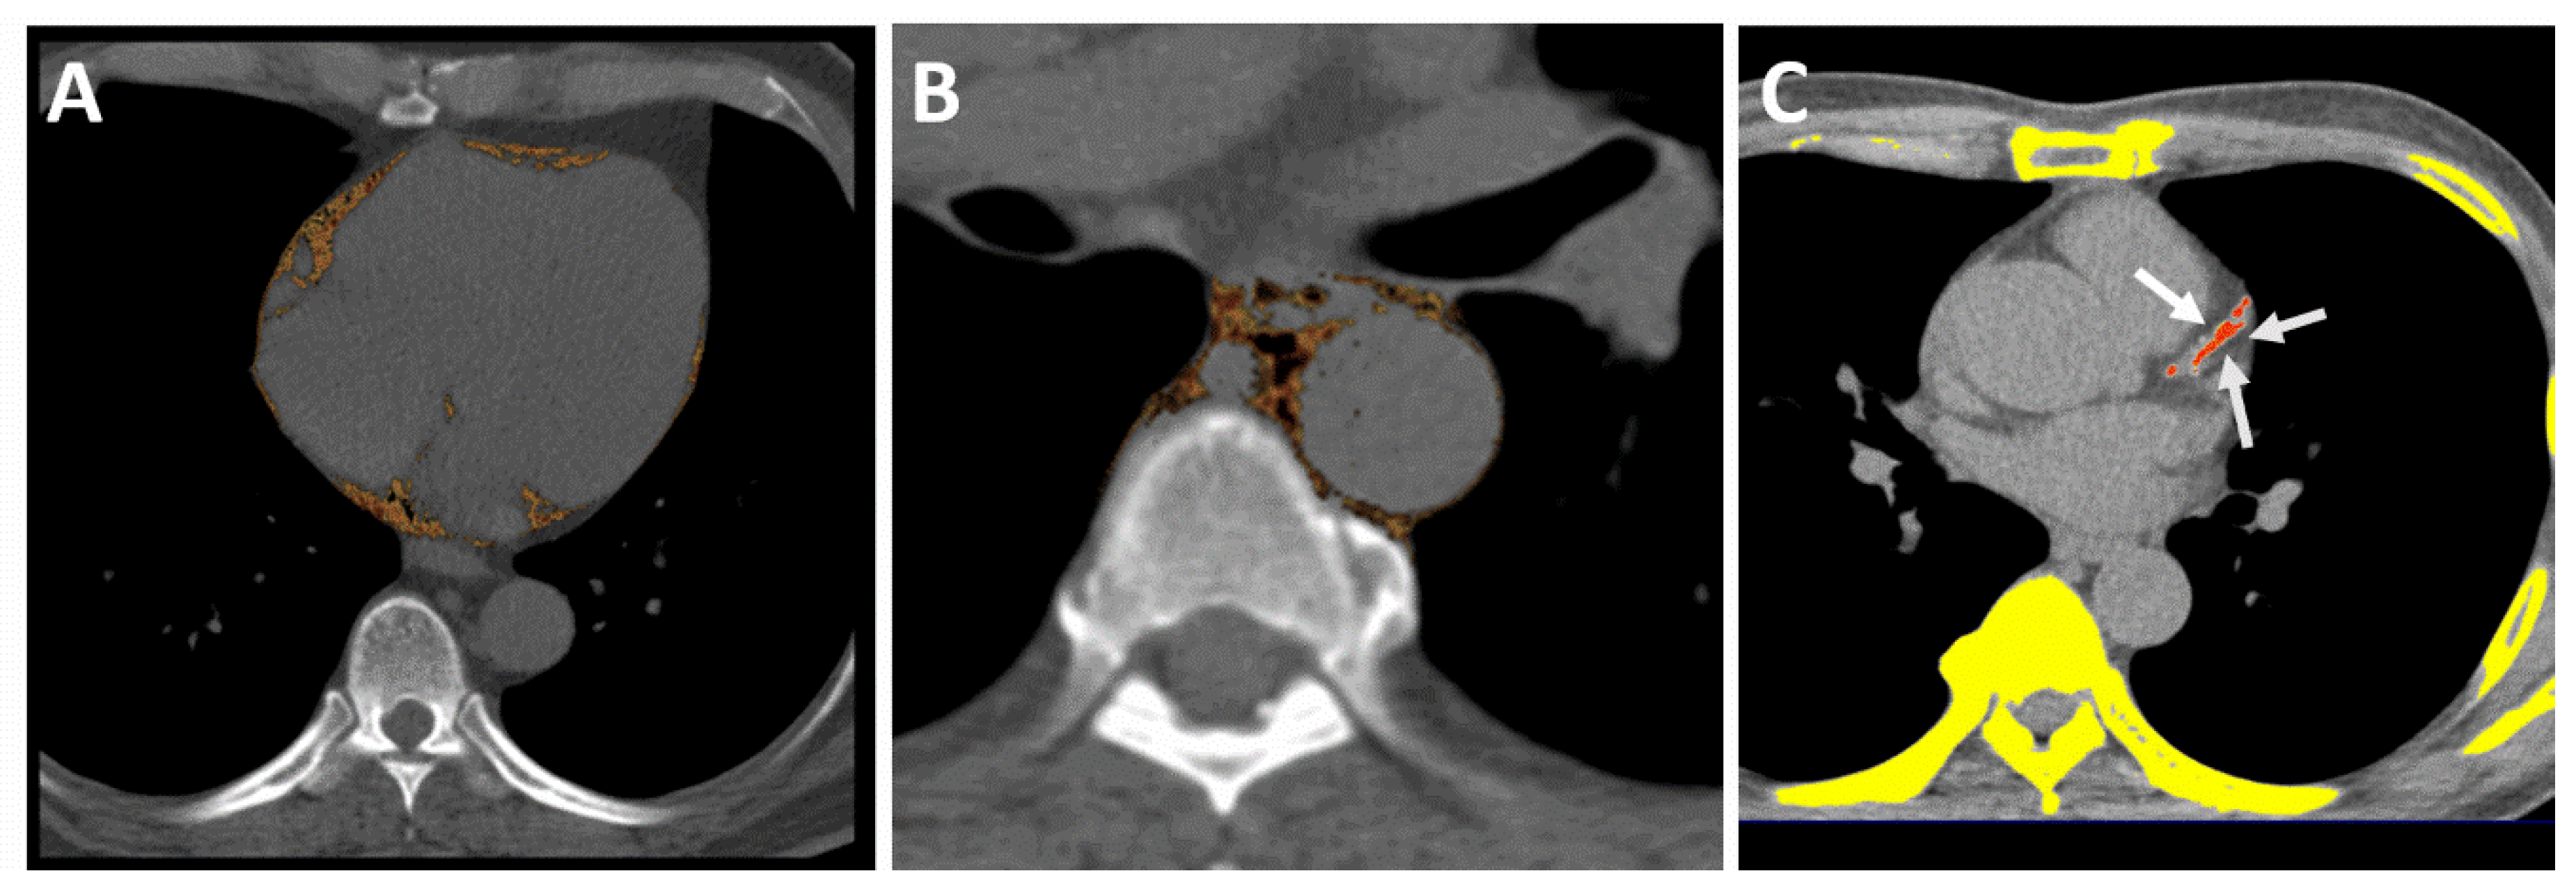

2.7. Measurements of PCF and TAT

2.8. Reproducibility for MDCT-Derived Visceral Adiposity